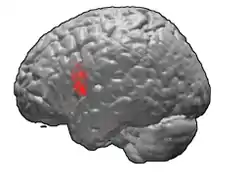

Brodmann area 44

Brodmann area 44, or BA44, is part of the frontal cortex in the human brain. Situated just anterior to premotor cortex (BA6) and on the lateral surface, inferior to BA9.

This area is also known as pars opercularis (of the inferior frontal gyrus), and it refers to a subdivision of the cytoarchitecturally defined frontal region of cerebral cortex. In the human it corresponds approximately to the opercular part of the inferior frontal gyrus. Thus, it is bounded caudally by the inferior precentral sulcus (H) and rostrally by the anterior ascending limb of lateral sulcus (H). It surrounds the diagonal sulcus (H). In the depth of the lateral sulcus it borders on the insula. Cytoarchitectonically it is bounded caudally and dorsally by the agranular frontal area 6, dorsally by the granular frontal area 9 and rostrally by the triangular part of inferior frontal gyrus (Brodmann area 45 BA 45).

Lateral view.